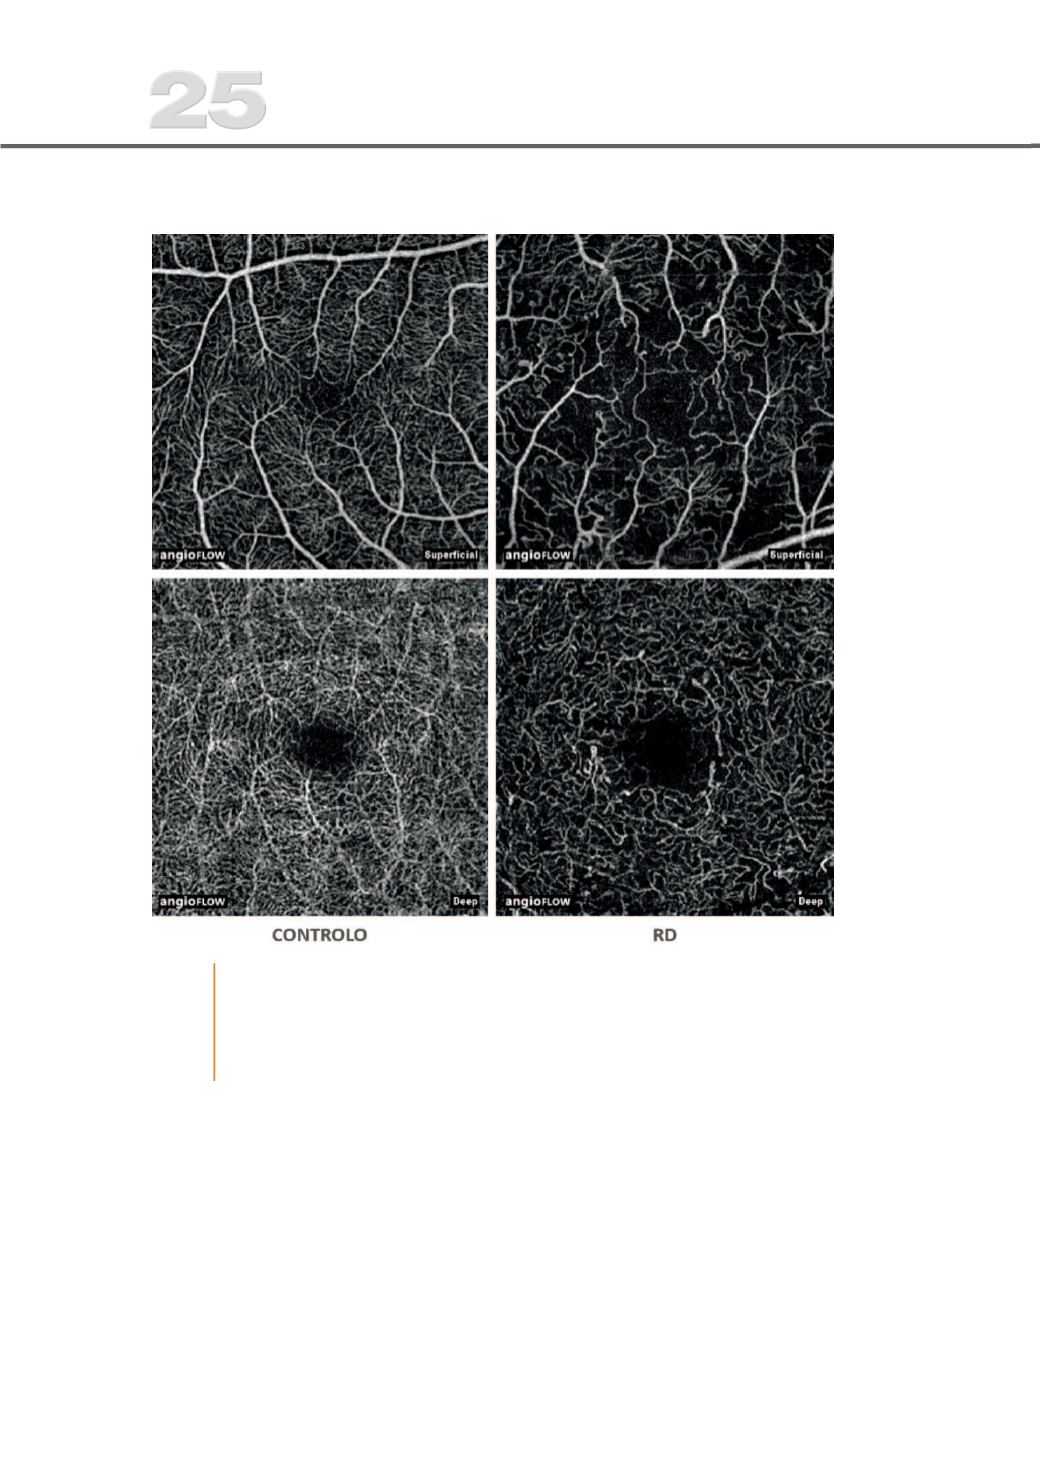

Fig. 1

OCTA de um controlo saudável (à esquerda) comparado com um doente com

RD sem edema macular (à direita). Em ambos os plexos super%cial e profundo

observa-se alargamento da área avascular central, alargamento dos espaços

intercapilares com dropout capilar, redução da densidade vascular, vasos

telangiectásicos e microaneurismas.